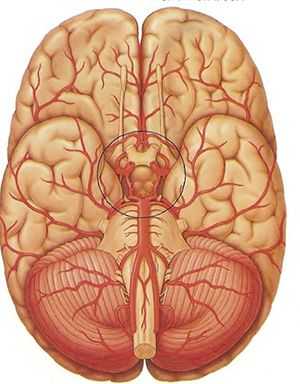

Строение Виллизиева круга

Классический Виллизиев круг образуют:

- Начальные отделы передних мозговых артерий (ПМА);

- Передняя соединительная артерия (ПСА);

- Задние мозговые артерии (ЗМА);

- Задние соединительные артерии (ЗСА);

- Надклиновидная часть внутренней сонной артерии (ВСА).

Перечисленные сосуды формируют подобие семиугольника. ВСА приносят кровь к мозгу из общих сонных и на основании мозга отдают ПМА, которые сообщаются друг с другом посредством ПСА. Задние мозговые артерии начинаются от основной, образующейся путем объединения двух позвоночных. Между ВСА и ЗМА есть связь — задние соединительные сосуды, в зависимости от диаметра получающие питание либо из системы внутренней сонной, либо из базилярной артерии.

Таким образом, образуется кольцо, связывающее два артериальных потока — из бассейна внутренней сонной и базилярной артерий, разные части которого могут взять на себя функцию обеспечения питанием тех частей мозга, которые испытывают недостаток крови при закупорке или сужении других составляющих мозговой сети.

Виллизиев круг находится в подпаутинном пространстве основания головного мозга, окружая своими составными элементами зрительную хиазму и образования среднего мозга, позади находится Варолиев мост, на поверхности которого расположена базилярная артерия.

Наибольшим постоянством в строении отличаются передние мозговые и сонные артерии, задние мозговые и соединительные ветви очень вариабельны в своей анатомии и особенностях ветвления. Однако изменения со стороны передней части Виллизиева круга носят большее клиническое значение вследствие более выраженной симптоматики и худшего прогноза.

Передняя мозговая артерия, как правило, хорошо сформирована и в норме ее просвет достигает полутора — двух с половиной миллиметров. ПСА такого же размера и длиной около сантиметра. Просвет левой внутренней сонной артерии в норме больше правой на 0,5-1 мм. Средняя мозговая артерия тоже имеет некоторую асимметричность в размерах: слева она толще, чем справа.

О строении этой части кровеносной системы

Существует множество вариантов построения артериального кольца основания мозга, но обязательными его компонентами являются артерии:

- передняя мозговая (её начальный фрагмент);

- задняя мозговая (на её начальном отрезке);

- соединительные (передняя и задние);

- внутренняя сонная (надклиновидный её фрагмент).

Основными сосудистыми магистралями являются 2 сонных и 2 позвоночных артерии (по одной с каждой стороны тела). Сонные входят в полость черепа посредством сонного канала, проходящего в пирамиде височной кости и открывающегося на её верхушке, позвоночные – миновав большое затылочное отверстие.

В классически-симметричном варианте позвоночные артерии, сливаясь, образуют одну мощную базилярную (основную), проходящую вдоль варолиева моста и дающую ветви для питания мозжечка и продолговатого мозга. Кпереди она разделяется на 2 задних соединительных (правую и левую), на этом же уровне создавая также 2 задних мозговых.

На уровне её впадения во внутреннюю сонную с обеих сторон от анастомоза в дистальном направлении ответвляются центральные мозговые артерии (левая и правая). Ответвления обеих внутренних сонных смыкаются впереди, образуя полукружие, от которого вперёд отходят 2 параллельно пролегающих передних мозговых артерии. Соединяющая же их сзади одиночная передняя соединительная перемычка является частью дуги, образованной слиянием ответвлений внутренних сонных артерий.